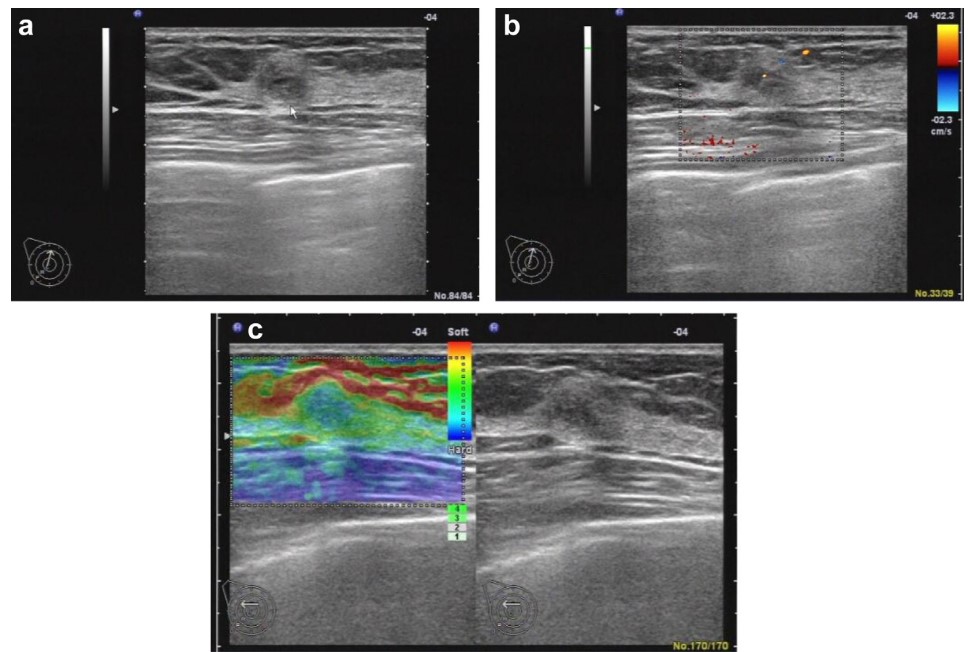

Availability, low cost, and safety make ultrasonography the most widely used clinical diagnostic tool, with applications ranging from breast cancer diagnosis to cervical lymph node detection. Conventional B-mode imaging is used to examine abnormal masses in tissues, Color Doppler imaging shows the distribution of blood vessels within tissues [268], while Strain Elastography (SE) is a qualitative technique and provides information on the relative stiffness between one tissue and another. For example, the combined use of Conventional B-mode imaging and Color Doppler is common in identifying cervical lymph nodes [4], diagnosing breast cancer [174, 173], and so forth [137, 191, 192]. Fig. 6 shows the US images of Conventional B-mode, Color Doppler, and Strain Elastography.

Refer to caption

Fig. 6: Breast ultrasound images of a 37-y-old woman with fibroadenoma. (a) Conventional B-mode, (b) Color Doppler, and (c) Strain elastography (SE) image [116].